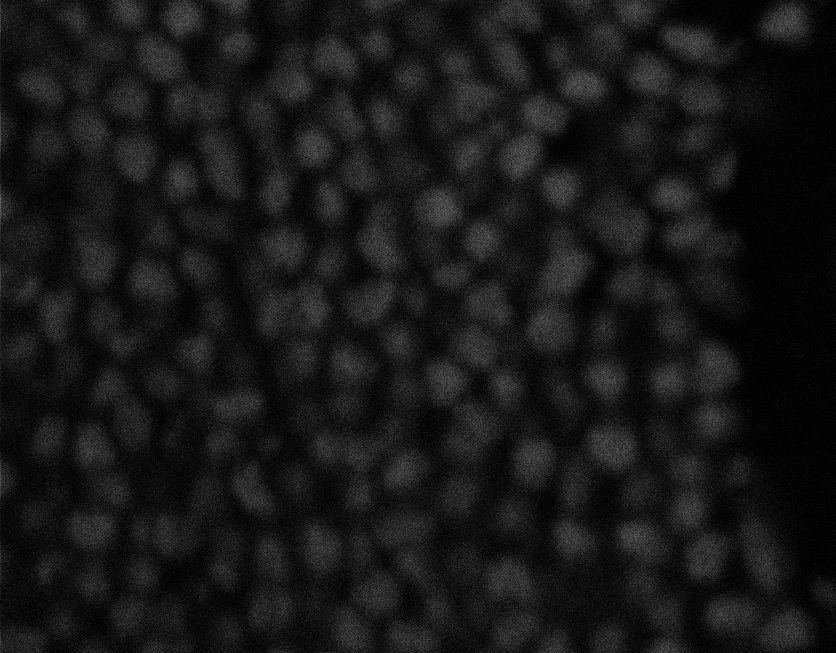

Nuclei

Nuclei - Bis

Nuclei - Bip

Nuclei - Bipolar